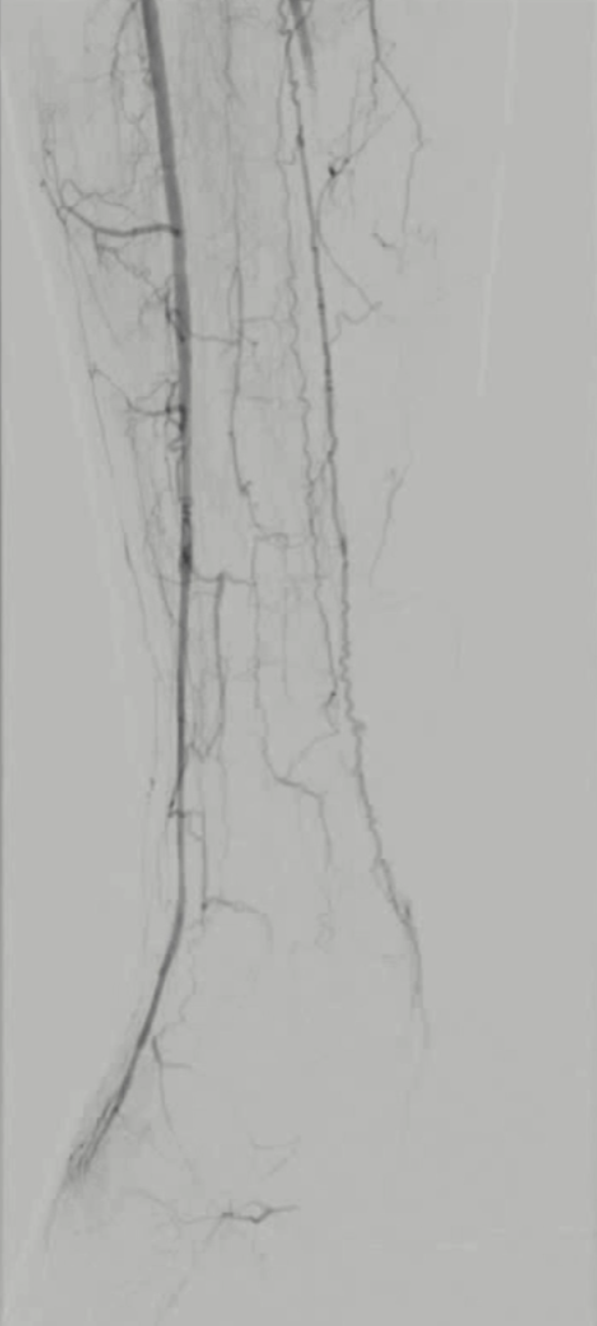

TAO动脉病变模式有 abrupt occlusion(突然闭塞)、Localized stenosis(局限性狭窄)、Moth-eaten stenosis(虫蚀样狭窄)等,还可能出现不规则侧支循环、侧支循环早期形成、树根样侧支、迂曲静脉等情况。

★ 病例2

51岁男性,间歇性跛行反复发作,经历多次PTA、CDT、支架植入等复杂治疗

2019.07 间歇性跛行3个月,PTA+CDT(8天)

2022.05,足趾麻木,支架植入

2023.05,间歇性跛行3个月,PTA+支架植入

治疗心得:50岁以上患者诊断困难;病灶进展迅速,治疗间隔缩短,难度增加;完全戒烟至关重要,但临床依从性差